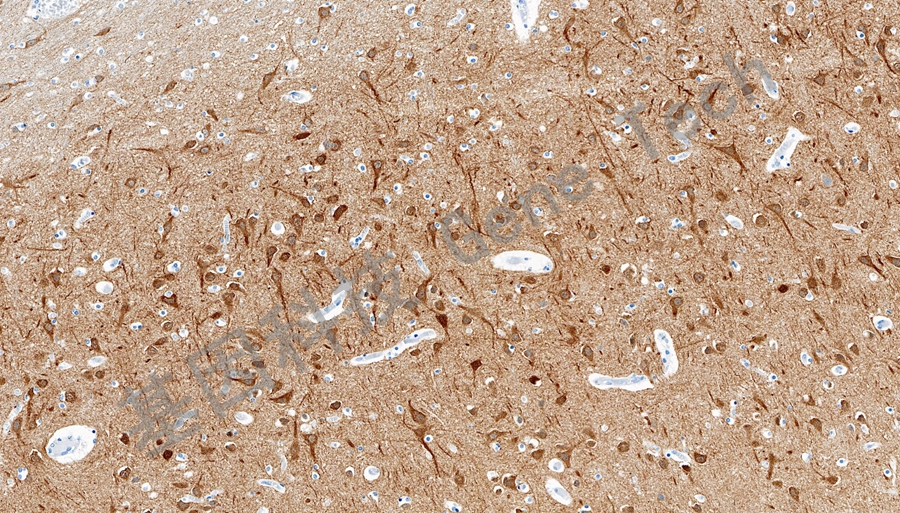

| 预处理:高pH热修复 | 阳性部位:细胞膜/细胞质 | 阳性对照:脑 |

| 脑石蜡切片,用 DCLK1(GT2565)染色,细胞膜/细胞质阳性,DAB 显色。 | ||